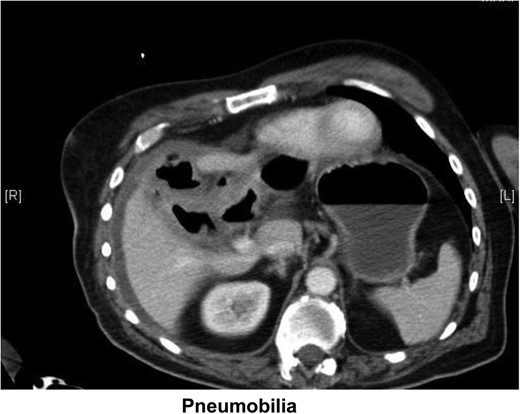

Pneumobilia with cholecystoduodenal fistula secondary to gallstone passage.

Small bowel obstruction with transition in the distal ileum probably due to obstructing gallstone (Fig. 2).

Given the paucity of information elicited from the patient in terms of history, the differential diagnoses were based on the results of the CT scan. The patient has small bowel obstruction the causes of which appeared to be either secondary to inguinal hernia or gallstone ileus. The treatment of which is very different, hernia being treated with an inguinal repair and gallstone ileus being treated with either laparoscopic resection or laparotomy. The decision was made to proceed to laparotomy on the basis that if the obstruction was secondary to hernia, a resection may well need to be performed, the same approach would also allow the resection for gallstone ileus. In addition, gallstone ileus was felt to be the more likely diagnosis given the presence of pneumobilia.